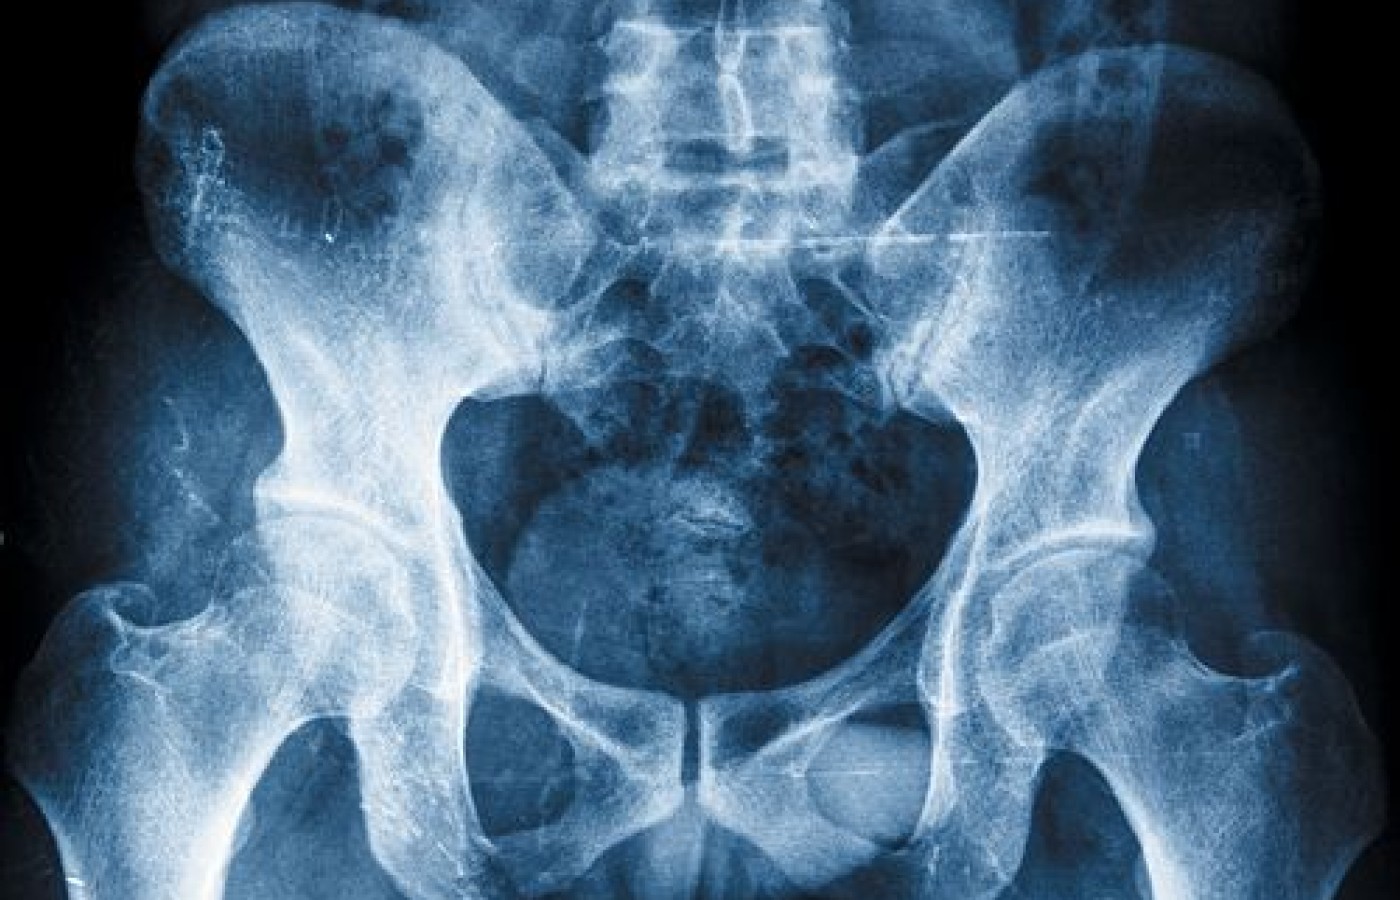

Unlocking Secrets of the Pelvis (Pt. 1)

Treatment of pelvic dysfunction that is effective and lasts beyond our patients walking out to the parking lot to their car requires observing and thinking about tri-planar movement of the pelvis. To understand balanced and symmetrical movement of the pelvis, we need to understand "myokinematics" or the study of motion produced by specific neuromuscular forces.1

The pelvis, as well as our entire body, needs to have as close to symmetrical muscle flexibility, strength and length as possible. Asymmetries in muscle strength, length and endurance with agonists and antagonists can eventually create dysfunction in movement and alignment patterns. Our rehabilitative goals need to include addressing these asymmetries effectively.1